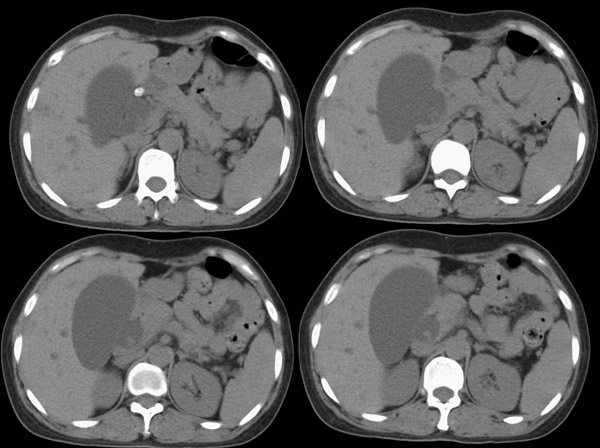

f42y近半月来无明显诱因出现右上腹疼痛之主诉就诊。疼痛多于饭后半小时发作,为持续性隐疼,呈阵发性、刀割样、钻顶样疼痛加剧,且向右肩背部放射,伴恶心、出汗、呕吐,呕吐内容物为胃内容物,无呕血,时有返酸、呃逆、烧心感,无腹胀、腹泻及黑便。时有发冷、发热(但体温不高);呕吐后腹疼稍有缓解,在当地诊所按“胃炎”对症治疗10天,效果不佳。血常规为:白细胞:9、8*109,中性64%,血红蛋白为151g/l,血小板为167*107。 既往有胆道蛔虫病史30余年,曾有呕虫史,否认肝炎及肺结核、溃疡病史。无外伤、手术及药物过敏史,陕西丹凤县四坪镇人,未去过疫区。

腹部ct平扫:(5mm层厚)

整个胆道系统内可见多发蛔虫钙化改变,胆道扩张.

胆总管结石并肝内外胆管扩张、肝左叶肝内胆管结石、胆囊大。